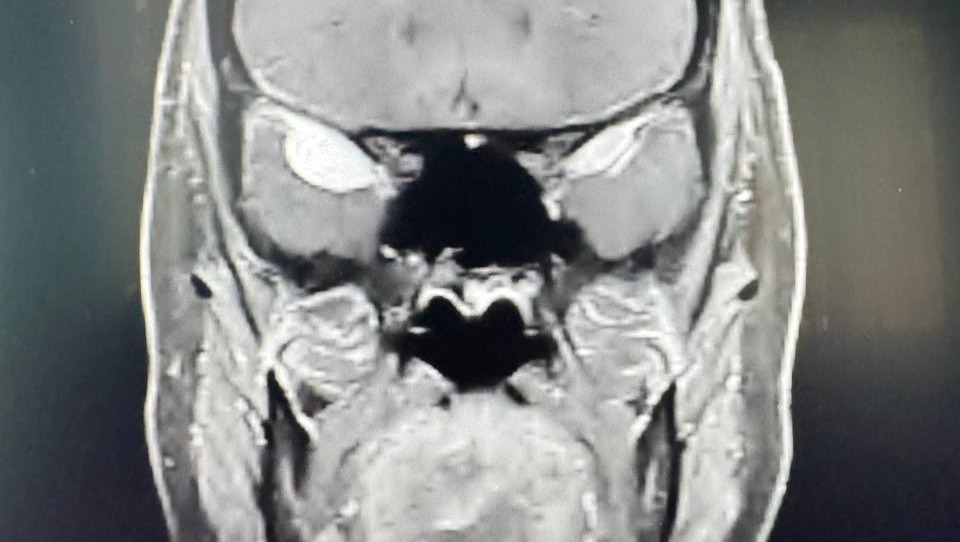

During this time, an MRI revealed two slow-growing, non-cancerous brain tumors (for the nerds: sphenoid wing meningiomas in the medial cranial fossa). One tumor is located at her hippocampus, which handles much of memory processing. Both are situated behind her eyes, which is affecting her visual processing. This explains many of the difficult symptoms she’s been battling over the last year.

Kristen has named her tumors collectively: The Angry Techno Viking

(raaaar I press on kia’s brain graaaaah)